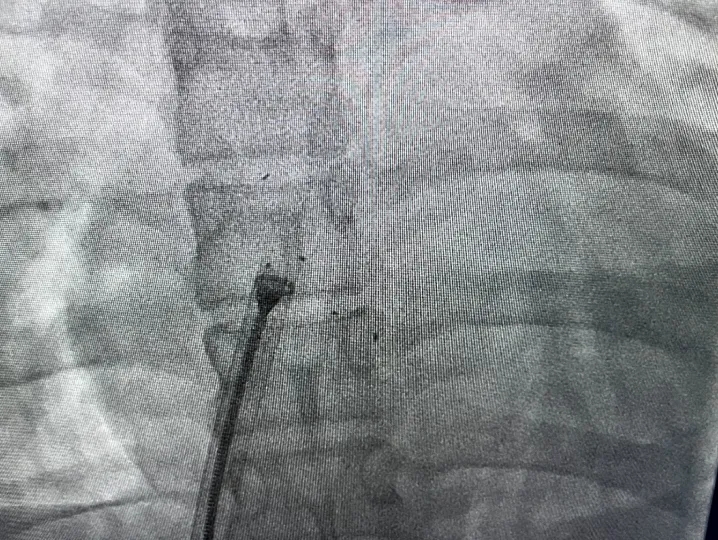

释放封堵器

DSA下观察5个Mark点整体移动,封堵器形态良好,封堵成功